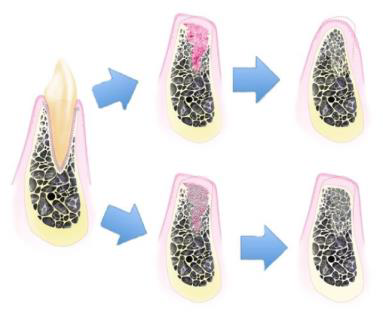

拔牙窩的癒合

| Day 0 | 血塊形成/止血 | 血塊除了止血外,內含許多 growth factor,會釋放訊號誘發骨形成。 |

| Day 4~5 | 血塊轉為 granulation tissue | 持續釋放 growth factor,並伴隨更多鈣化物形成。 |

| Day 5~16 | 轉變為 connective tissue matrix | 拔牙窩的 bundle bone 開始吸收,讓周圍骨髓空間的血管增生,逐漸形成 cancellous bone。 |

| Week 3~6 | 骨生成與軟組織屏障 | woven bone 從拔牙窩周邊開始形成。 |

| Week 5~10 | 骨重塑形成 trabecular bone | 傳統觀念認為骨頭鈣化至此階段後才適合植牙。 |

- Bundle Bone 無法被 Preserve

- Bundle bone是骨前驅細胞的重要來源,拔牙窩越完整,自癒能力越好。

- 上下顎拔牙後,唇頰側的骨板易吸收

- 癒合皆偏腭/舌側